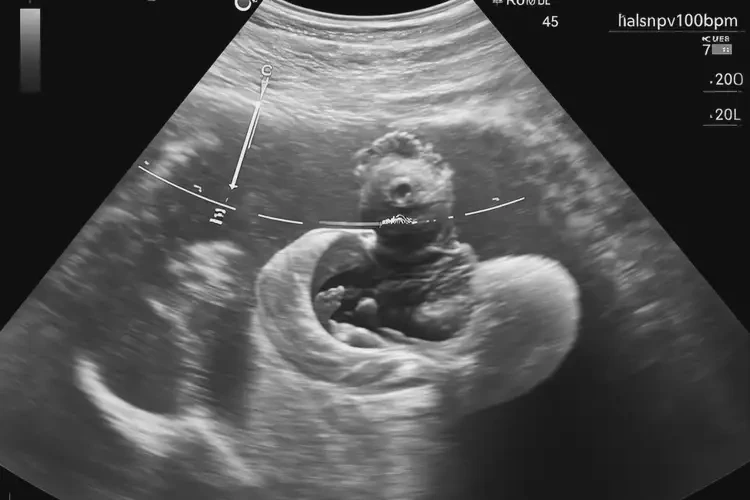

懷孕第7周胎心100怎么回事

胎心100次/分鐘

在懷孕第7周,胎心率約為100次/分鐘,這屬于正常范圍。胎心率是指胎兒心臟每分鐘跳動(dòng)的次數(shù),是評(píng)估胎兒健康狀況的重要指標(biāo)之一。以下是關(guān)于懷孕第7周胎心率的詳細(xì)解釋:

懷孕第7周胎心100怎么回事(圖1)